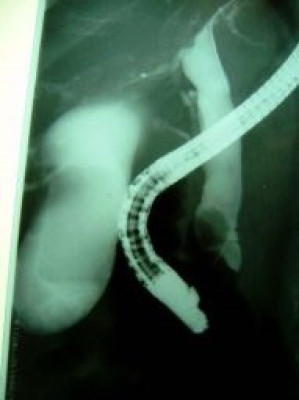

Colelitiasis y coledocolitiasis ERCP

Envíado por Dr. Carlos Miguel Zavaleta Consuegra